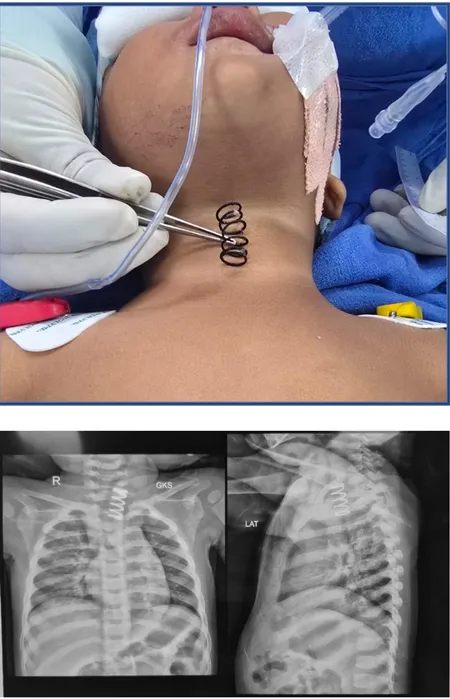

एम्स के डॉक्टरों ने 14 महीने के बच्चे की फूड पाइप से 2 इंच लंबा मेटल स्प्रिंग निकाला

नई दिल्ली। ऑल इंडिया इंस्टीट्यूट ऑफ मेडिकल साइंसेस (एम्स) के डॉक्टरों ने गुरुवार को ऑपरेशन कर 14 महीने की एक बच्ची की जान बचाई। बच्ची ने गलती से 2 इंच लंबा धातु का स्प्रिंग निगल लिया था। एम्स ने एक आधिकारिक बयान में कहा कि धातु का स्प्रिंग खाद्य नली (आंत्र) में फंस गया था, उसे एंडोस्कोपिक सर्जरी के जरिए सफलतापूर्वक निकाला गया।

बच्ची यमुनानगर की रहने वाली है। उसको लगातार उल्टी होने और दो दिन तक खाने-पीने में असमर्थ रहने पर अस्पताल लाया गया। बताया गया, “जांच के दौरान एक्स-रे में देखा गया कि बच्चे की ऊपरी खाद्य नली में एक बड़ा धातु का स्प्रिंग फंसा हुआ था। साथ ही म्यूकोसा पर अल्सरेशन भी दिखाई दिए।”

पेडियाट्रिक सर्जरी विभाग के प्रोफेसर डॉ. विशाल जैन ने बातचीत करते हुए कहा, “स्प्रिंग खाद्य नली के ऊपरी हिस्से में फंसा था। इसकी मोटाई सामान्य पेन के स्प्रिंग से काफी ज्यादा थी। यह लगभग आधा इंच चौड़ा और 1.5 से 2 इंच लंबा था।” उन्होंने बताया कि पहले इसे देहरादून के एक प्राइवेट अस्पताल में एंडोस्कोपिक तरीके से निकालने की कोशिश की गई, लेकिन खाद्य नली में सूजन और घाव होने के कारण यह जोखिमपूर्ण था, इसलिए बच्ची को तुरंत एम्स भेजा गया।

डॉ. जैन और उनकी टीम ने ऑपरेटिंग रूम में उन्नत एंडोस्कोपिक तकनीक का इस्तेमाल किया। स्प्रिंग को सावधानी से घुमाकर निकाला गया ताकि नली में कोई छेद न हो। एम्स ने कहा, “सर्जरी के बाद बच्ची की स्थिति जल्दी सुधरी और अगले दिन उसे सामान्य रूप से खाना शुरू कराया गया।”डॉ. जैन ने माता-पिता को सलाह दी कि स्प्रिंग, बैटरी, सिक्के और छोटे खिलौनों के हिस्से जैसी चीजें बच्चों की पहुंच से दूर रखें, क्योंकि इन्हें निगलना जानलेवा हो सकता है। उन्होंने कहा कि अगर बच्चा कुछ निगल ले तो तुरंत डॉक्टर के पास ले जाएं ताकि डॉक्टर वस्तु का आकार देखकर उचित उपचार कर सकें।